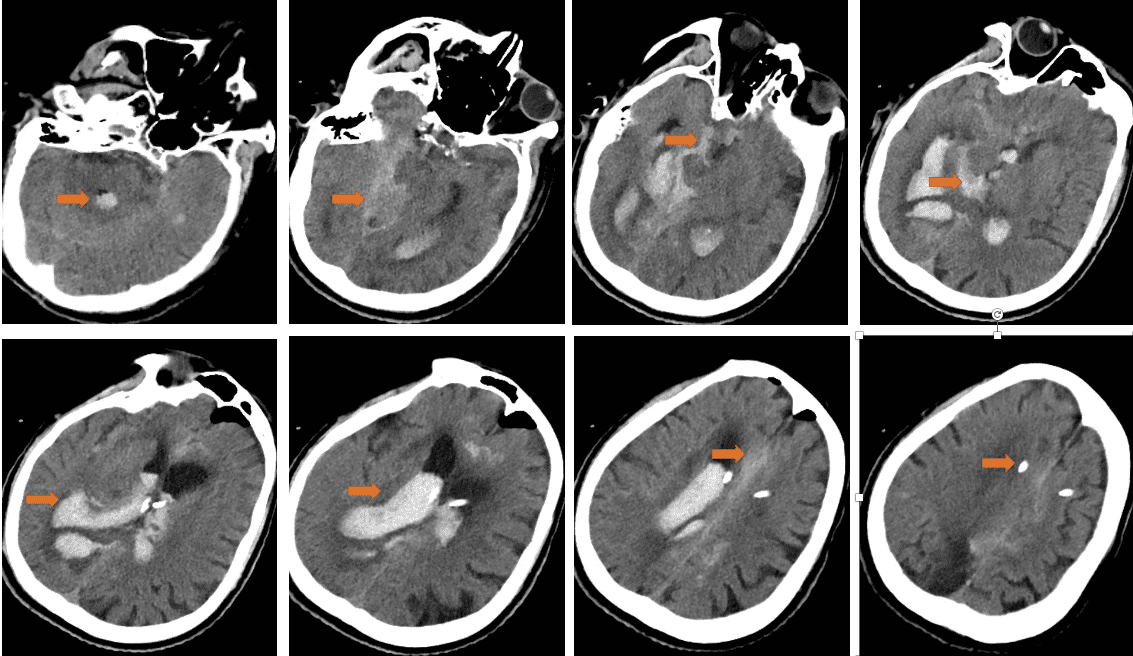

头CT:右侧侧脑室见片状高密度影,脑室内见多发不规则高密度影。双侧大脑半球脑沟内高密度影,额部颅板下见积气影。小脑、右顶叶、双侧额叶、放射冠区、基底节区见半片状低密度影,局部近液体密度影;脑室及脑池系统扩张。双侧脑沟裂增宽、加深,中线结构居中。

1、入院后联系神经外科,鉴于出血量大,征得家属同意后行颅内出血置管引流术,间断引流血性液体,复查CT提示出血减轻,意识也曾一度清醒,示意肢体

可简单活动;

2、8月3日患者意识成昏迷状态,复查CT提示再次出血,急诊ICU告知病情加重预后不良,家属经商议后放弃治疗。三、初步诊断

PS:复盘患者CT情况,颅内出血大部分集中在右侧颞叶,累及中脑环池,且破入侧脑室,考虑患者存在后交通动脉瘤可能性大。